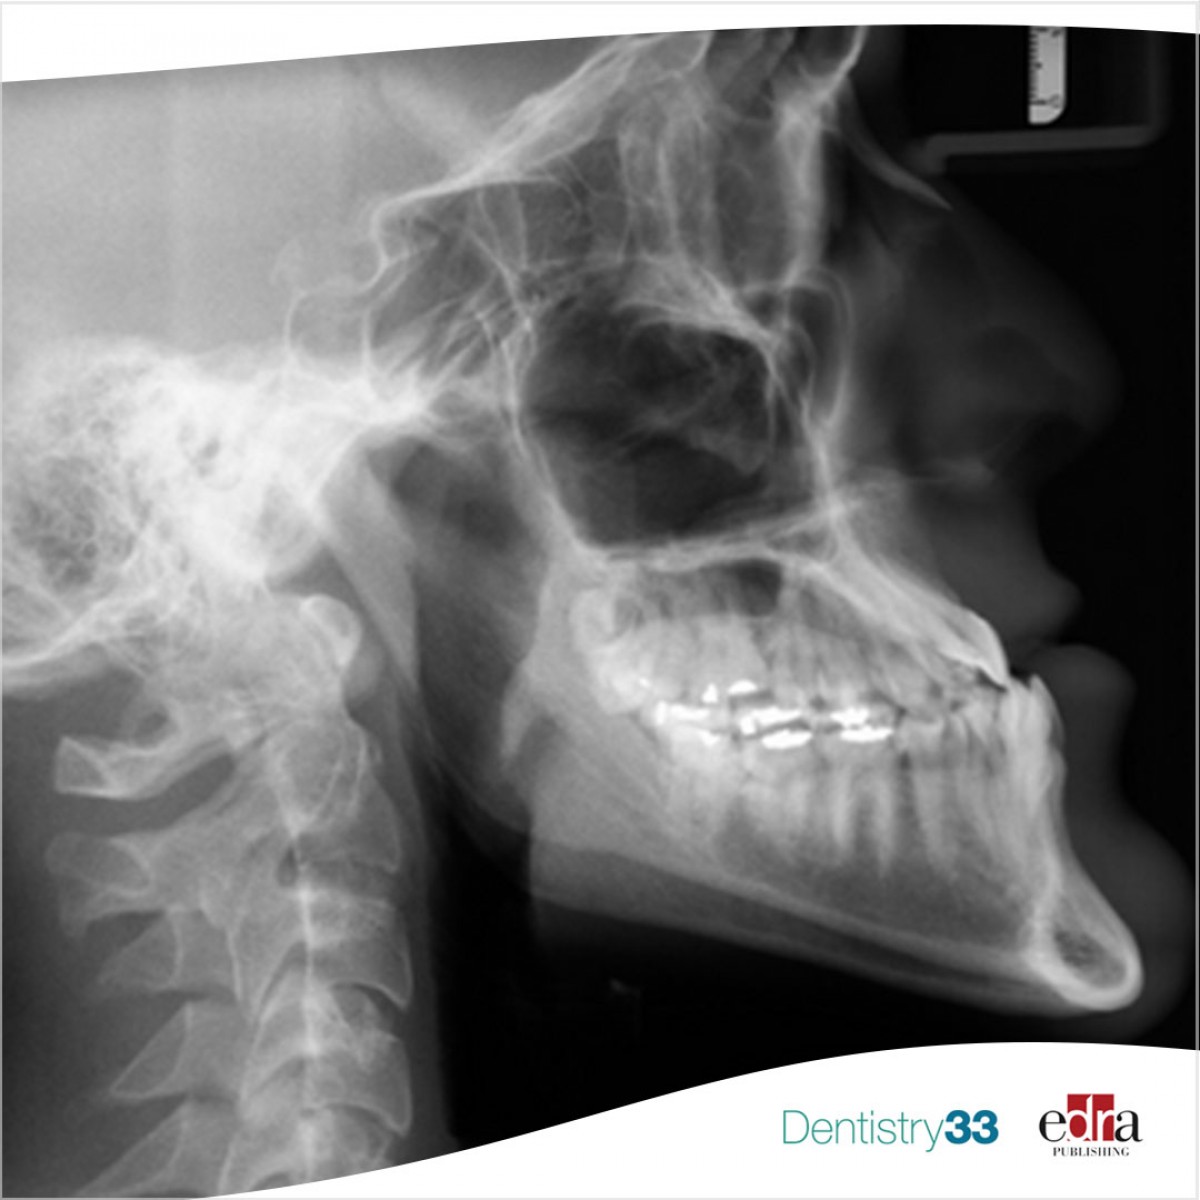

Impact of chronic drug intake on the cure of endodontic pathologies

The relationship between systemic health and the pathogenesis or cure of endodontic disease has received much attention in the last two decades.

Several literature studies have documented this correlation, especially in chronic diseases such as diabetes mellitus (DM), cardiovascular diseases (CVD), kidney diseases, gastrointestinal diseases, and rheumatoid arthritis.

Recent systematic reviews have recognized the relationship between endodontic success and various systemic diseases, such as DM, CVD, human immunodeficiency virus infection, and drugs, such as oral bisphosphonates (BPs). Studies have also confirmed the possible influence of MD and CVD on the outcome of endodontics-treated teeth.

Most patients suffering from these diseases are treated for these and other conditions with potent drugs that have important biologic roles, including anti-inflammatory, antimicrobial, and osteoconductive roles, roles relevant to the pathogenesis or cure of pulpitis and apical periodontitis (AP).